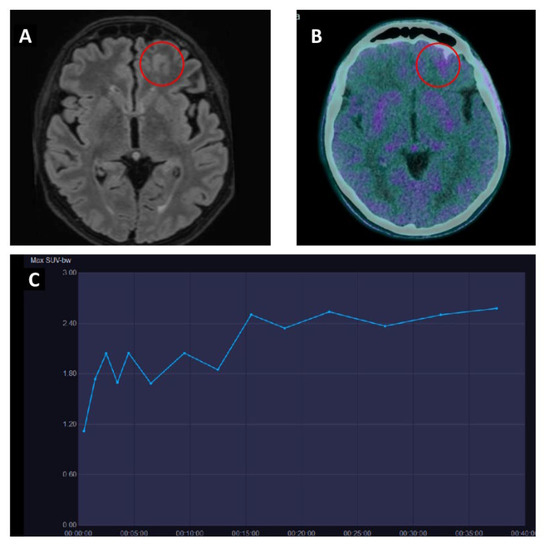

- Horky, L.L.; Hsiao, E.M.; Weiss, S.E.; Drappatz, J.; Gerbaudo, V.H. Dual Phase FDG-PET Imaging of Brain Metastases Provides Superior Assessment of Recurrence versus Post-Treatment Necrosis. J. Neurooncol. 2011, 103, 137–146. [Google Scholar] [CrossRef]

- Ceccon, G.; Lohmann, P.; Stoffels, G.; Judov, N.; Filss, C.P.; Rapp, M.; Bauer, E.; Hamisch, C.; Ruge, M.I.; Kocher, M.; et al. Dynamic O-(2-18F-Fluoroethyl)-L-Tyrosine Positron Emission Tomography Differentiates Brain Metastasis Recurrence from Radiation Injury after Radiotherapy. Neuro. Oncol. 2017, 19, 281–288. [Google Scholar] [CrossRef]